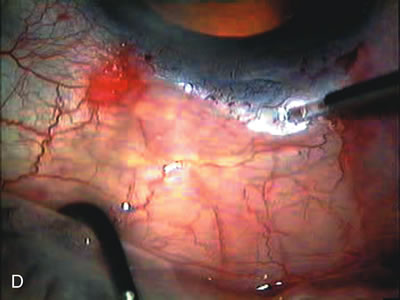

Fig. 4. Viscocanalostomy with deep sclerectomy and phacoemulsification. Nonpenetrating filtration procedures (NPFS) may be combined with phacoemulsification. Patients with mild disc damage and a history of limited topical drug therapy are the best candidates. Patients who require an IOP in the low teens are not good candidates for NPFS. By definition, NPFS is designed to lower IOP without penetrating into the anterior chamber, thereby avoiding the complications associated with trabeculectomy. Viscocanalostomy is intended to allow aqueous to percolate through a trabeculodescemetic membrane into a subscleral cavern created by the deep sclerectomy. The aqueous diffuses from the cavern into the dilated ostia of Schlemm's canal and into the episcleral venous plexus. A. Fashion a uniform 300-micron superficial scleral flap 1 mm into clear cornea. B. Construct a second 600-micron deep flap that facilitates the unroofing of Schlemm's canal, seen as the darker area. C. Use viscoelastic to dilate the ostia of Schlemm's canal. The major problem with viscocanalostomy is the eventual closure of the ostium decreasing flow to the episcleral plexus. D. Dissect the deep flap anteriorly into clear cornea creating the trabeculodescemetic membrane. This membrane is clearly seen between the scleral spur and the bend of the deep flap. The integrity of this membrane ensures the nonpenetrating portion of the surgery. Another problem with NPFS is the eventual fibrosis of this initially transparent membrane requiring goniopuncture. E. Deep sclerectomy gets its name from removal of the deep flap. Removal of this flap creates the potential subscleral space for accumulation of aqueous before it enters Schlemm's canal and exits the episcleral venous plexus. After removal of the deep flap, the superficial flap is sutured into place and conjunctiva closed. Approximately half of these procedures develop a shallow bleb.